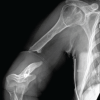

A 24-year-old male patient presented to our clinic with complaints of intermittent atraumatic effusion in his right knee for the past 3 months, accompanied by progressively worsening pain. His symptoms were exacerbated after joining the army, with pain and functional limitations, significantly impairing his quality of life and daily activities. The patient was overweight (Body Mass Index – BMI: 27.2 kg/m2) but otherwise healthy. On physical examination, knee effusion and palpable crepitus were observed during active and passive range of motion. His Lysholm Knee Score was 67, and the International Knee Documentation Committee (IKDC) score was 71.3%. Plain radiographs revealed a large osteochondral lesion in the lateral femoral condyle (Fig. 1), which was further evaluated using computed tomography (CT) scan and magnetic resonance imaging (MRI) (Fig. 2 and 3). A three-dimensional printed model of the patient’s distal femur, based on the CT imaging, was created to evaluate the focal articular defect and facilitate the pre-operative planning (Fig. 4).